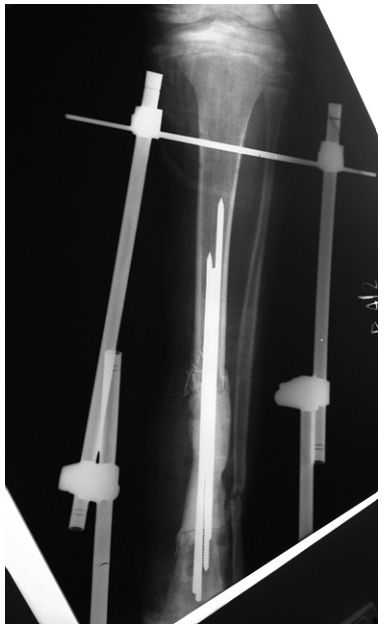

➤ 3、采用带抗生素的骨水泥做成的spacer(间隔块),比如下图里用3根克氏针+骨水泥做成的间隔块;

➤ 4、并用外固定支架支撑。